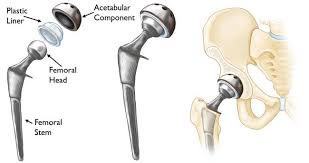

اسعار مفصل الفخد الصناعيه

التكلفة دائما ما تكون الشئ المحير لدي كثيرين، قبل الإقدام علي أى عملية، ولكن عليك أن تعلم أن تكلفة أو سعر تغيير مفصل الفخذ الصناعي تتفاوت على حسب عدة أمور منها:

6- نوع المفصل الصناعي المناسب لحالة المريض فالمفاصل اللاأسمنتية تكون أغلى سعرا من المفاصل الأسمنتية.

7- نوع المواد المستخدمة فى الصناعة المفصل: فالمفاصل التقليدية ذات السطح المعدني على البلاستيكية تكون أقل كلفة من مفاصل الفخذ الصناعية ذات الاسطح السيراميكية والتى تناسب أكثر صغار السن كما أن المقاسات الكبيرة من رأس مفصل الفخذ تكون ذات سعر أعلى مثل سعر مفصل الركبة الأمريكي.

ببساطه، المفصل مكون جزئين مصنوعين من سبيكه معدنيه تتحمل الضغوط والأحمال لمده سنوات طويله وتثبت القطعتين علي الأجزاء المساهمه في مفصل الركبه من أسفل عظمه الفخذ وأعلي عظمه القصبه وتثبت بين السطحين المعدنيين قطعه مصنوعه من اللدائن البلاستيك (بولي اثيلين) وتسمح هذه القطعه بالحركه بنعومه ويسر.

كل مفصل ركبة بديل يتألف من ثلاث أجزاء: جزء خاص بالفخذ وآخر خاص بالساق وجزء قائم على اللدائن يتمركز على الظنبوب.

مكونات الفخذ تتكون عادةً من وصلة معدنية وتستبدل الأسطح المهترئة من عظم الفخذ، الجزء الخاص بالساق يتكون من تيتانيوم الأجزاء المهترئة من عظم الظنبوب، فوق ذلك يتم وضع محيط الانزلاق القائم على اللدائن (بولي ايثيلين)، الذي يستبدل بدوره الفجوة المفصلية صناعيا، إحدى الخيارات يتمثل في إزالة الجزء الخلفي من الرضفة واستبداله بمعدن؛ ولكن هذا الخيار الأخير نادراً ما يجد التطبيق تكلفة عملية الركبة الصناعية.

ويتكون مفصل الركبة الصناعي من جزء معدني يغطي سطح عظمة الفخذ وآخر يغطي القصبة وبينهما مادة بلاستيكية بيضاء ذات قوة عالية لمنع الأحتكاك بينهم وفى حالات قليلة قد يتم تركيب جزء بلاستيكي يغطي سطح عظمة الصابونة (الردفة) ويتم تثبيت هذه الأجزاء فى العظام عادة بواسطة مادة تسمى الأسمنت العظمي وهناك انواع من مفاصل الركبة الصناعية يتم تركيبها بدون أسمنت طبي ولكن إستخدامها غير شائع نظرا لإرتفاع تكلفنها وعدم ثبوت تميزها عن المفاصل الأسمنتيه.